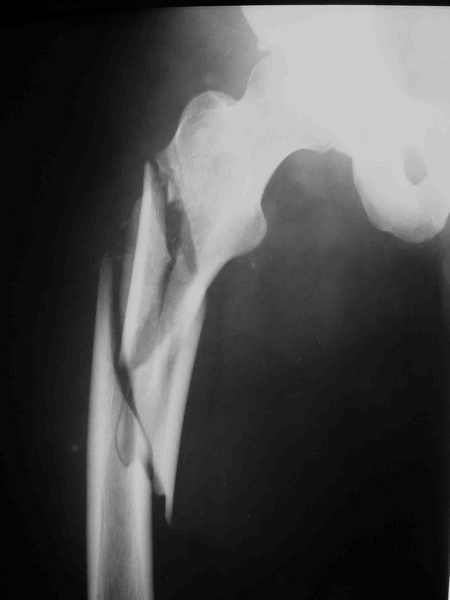

ПЕРЕСМАТРИВАЛ РАЗНЫЕ СНИМКИ И НАШЕЛ НА ЭТУ ТЕМУ ФОРУМА СНИМОК. БОЛЬНОЙ БЫЛ ПРООПЕРИРОВАН НА ПРАВОЕ БЕДРО ПОСЛЕ ЧЕГО СДЕЛАН ТАЗ В ЦЕЛОМ. ВОТ ЧТО НАШЛОСЬ.

КАКОЕ ВАШЕ МНЕНИЕ О ТАКТИКЕ.

ДУМАЮ ПРОШЛО ОКОЛО 10 ДНЕЙ.